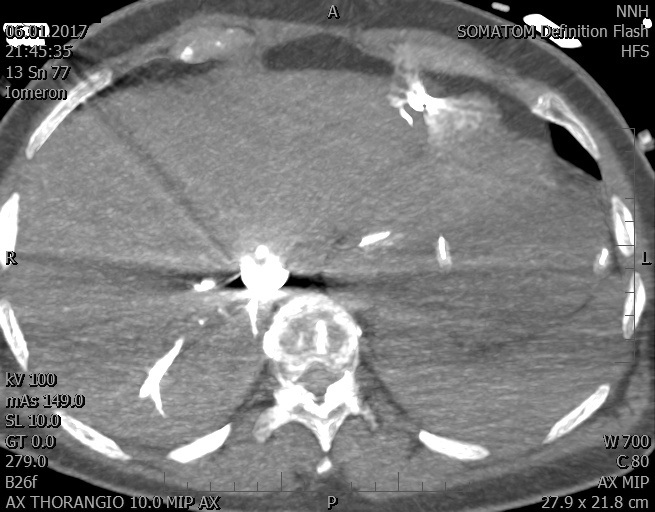

Video 2 - Echokardiograficky byla zjištěna těžká dysfunkce dilatační levé komory s nezvětšenou pravou komorou.Pro nejasnou příčinu zástavy jsme provedli i vyšetření výpočetní tomografií (CT), které vyloučilo plicní embolizaci (série 1 - soubory na konci článku). V den přijetí při přetrvávající oběhové nestabilitě byla nemocná opakovaně defibrilována pro fibrilaci komor se stabilizací rytmu po podání amiodaronu a mesocainu. Dle hemodynamických měření se jednalo o těžký kombinovaný šok. Vstupní laboratorní vyšetření bylo bez větších pozoruhodností. Posléze jsme doplnili anamnézu od příbuzných a zjistili, že pacientka užila do dvou hodin před srdeční zástavou první tabletu amoxicilinu na lehký respirační infekt. Při nevýtěžnosti vstupních vyšetření a nových anamnestických informacích jsme doplnili 14 hodin po kolapsu vyšetření koncentrace tryptázy v séru, která byla extrémně zvýšena (tabulka 2), což nás vedlo k podezření na anafylaxi.